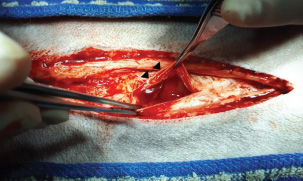

To correct hypovolemic shock prior to surgery, lactated Ringer’s solution was administered intravenously (IV) at a rate of 90 ml/kg/hour. Additionally, one unit of whole blood was transfused to restore circulating volume. Premedication consisted of butorphanol (0.2 mg/kg IV; Butophan Inj., Myungmoon Pharm. Co., Ltd., Seoul, Republic of Korea) and cefazolin (30 mg/kg IV; Safdin, Daehan New Pharm Co., Ltd, Republic of Korea). Anesthesia was induced with propofol (6 mg/kg IV; Provive 1%, Myungmoon Pharm. Co., Ltd., Seoul, Republic of Korea) and maintained with 1.2%–1.4% isoflurane (Forane sol., Choongwae. Co., Ltd., Seoul, Republic of Korea) delivered in 100% oxygen. Lactated Ringer’s solution was administered at 10 ml/kg/hour IV throughout the surgical procedure. Exploratory laparotomy via a ventral midline incision confirmed the presence of hemoperitoneum (Fig. 3). A firm, round, lobulated mass measuring 6 cm in height, 7 cm in width, and 8.5 cm in length was identified in the right pancreatic lobe. The mass was firmly adhered to the jejunal mesentery and adjacent mesenteric vessels (Fig. 4), consistent with its location in the caudal portion of the right pancreatic limb. Active bleeding was observed from a pancreatic vessel adjacent to the mass (Fig. 5). Blunt dissection with moistened cotton swabs was used to separate the right lobe from surrounding vessels. The pancreatic vessels were ligated using a bipolar vessel-sealing device (LigaSure; Valleylab, Tyco Healthcare Group, Boulder, CO, USA). A ligature was placed approximately 2 cm proximal to the tumor within the pancreatic parenchyma, and a portion of normal pancreas was excised. Approximately 13 cm of jejunum and the associated mesentery were also resected, followed by an end-to-end jejunal anastomosis. No gross metastatic lesions were observed in the liver or spleen. All excised tissues were fixed in 10% buffered formalin for histopathological examination.

Fig. 4. During exploratory laparotomy, a firm, round, and lobulated mass approximately 6 cm in height, 7 cm in width, and 8.5 cm in length (black arrowhead) was found in the right lobe of the pancreas. This mass strongly adhered to the jejunal mesentery and mesenteric vessels.